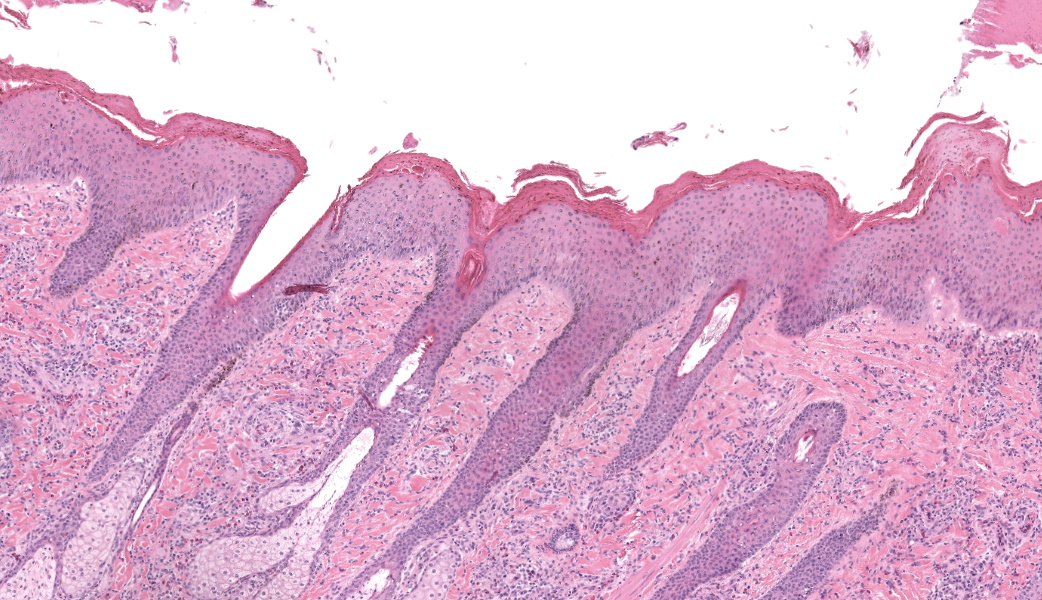

Haired skin, coronary band. Expanding and infiltrating the entire dermis are multifocal to coalescing perivascular, periadnexal and interstitial aggregates of moderate numbers of lymphocytes, eosinophils and histiocytes, fewer plasma cells and occasional neutrophils. Multifocally within dermis are few small areas of intensely eosinophilic, fragmented collagen fibers admixed with eosinophilic cellular- and basophilic nuclear debris, surrounded by epitheloid macrophages and multinucleated giant cells (eosinophilic granulomas). Intramurally and intraluminally within multiple hair follicles are moderate numbers of eosinophils, lymphocytes and histiocytes and few multinucleated giant cells (mural and luminal folliculitis), and adjacent follicular epithelium display moderate spongiosis. In the dermal-epidermal interface, there is a multifocal mild edema. The epidermis shows mild lymphocytic infiltration, mild spongiosis and occasional apoptotic keratinocyte, diffuse mild acanthosis and mild rete ridge formation (epidermal hyperplasia), moderate parakeratotic and orthokeratotic hyperkeratosis and multifocal erosions and ulcerations, the latter being covered by large serocellular crusts spanning over several adnexal units. Serocellular crusts show abundant viable and degenerated neutrophils, occasional eosinophil, cellular debris, fibrin, free keratin and hair fragments and occasional small basophilic bacterial colonies. There are also small epidermal intracorneal pustules multifocally. Several arteriolar walls in deep dermis show infiltration of few eosinophils and lymphocytes (vasculitis). The deep dermis displays mild diffuse edema.Contributor's Morphologic Diagnoses:

Haired skin, coronary band: Dermatitis and folliculitis, lymphoplasmacytic, histiocytic and eosinophilic, multifocal to coalescing, moderate, with eosinophilic granulomas, epidermal intracorneal pustules, serocellular crusts and orthokeratotic and parakeratotic hyperkeratosisEquine multisystemic eosinophilic epitheliotropic disease (MEED)